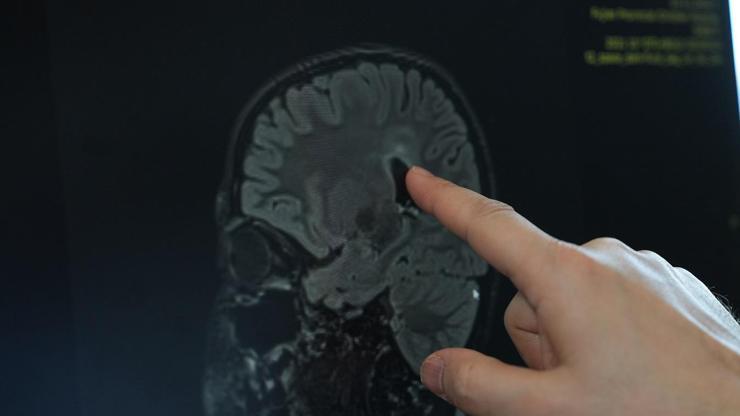

Serebral Palsi haberleri

serebral palsi haberi sayfasında en son yaşanan serebral palsi gelişmeleri ile birlikte geçmişten bugüne CNN Türk'e eklenen serebral palsi haber başlıkları yer almaktadır. Son dakika serebral palsi haberleri de dahil olmak üzere toplam 38 haber bulunmuştur.